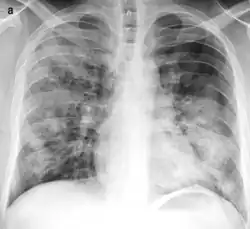

On gross pathology there are typically multiple foci of consolidation present in the basal lobes of the human lung, often bilateral. These lesions are 2–4 cm in diameter, grey-yellow, dry, often centered on a bronchiole, poorly delimited, and with the tendency to confluence, especially in children.

Light microscopy typically shows neutrophils in bronchi, bronchioles and adjacent alveolar spaces.[2]